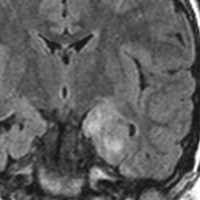

脳幹部から発生した退形成性神経節膠腫 grade 3

軽い右顔面神経麻痺で発症した小児で,右上下肢の軽度の失調症もありました。脳幹部(橋)の右背側から発生した腫瘍で,軽度の閉塞性水頭症を合併しています。左はT2強調画像で,橋の右側ににじむような浸潤像と浮腫があります。腫瘍は小嚢胞を形成してT2強調画像で実質は等信号です。真ん中の画像はCISS画像で橋が腫大しているのがよくわかります。右側はガドリニウム増強像で,全体が増強されてまだらな増強所見となっています。正中後頭下開頭で全摘出 gross total removal して,局所放射線治療とtemozolomide, cisplatine, etoposide, gleevec, hydoreaなどの化学療法を行いましたが,手術後4ヶ月で激しい播種再発を来しました。